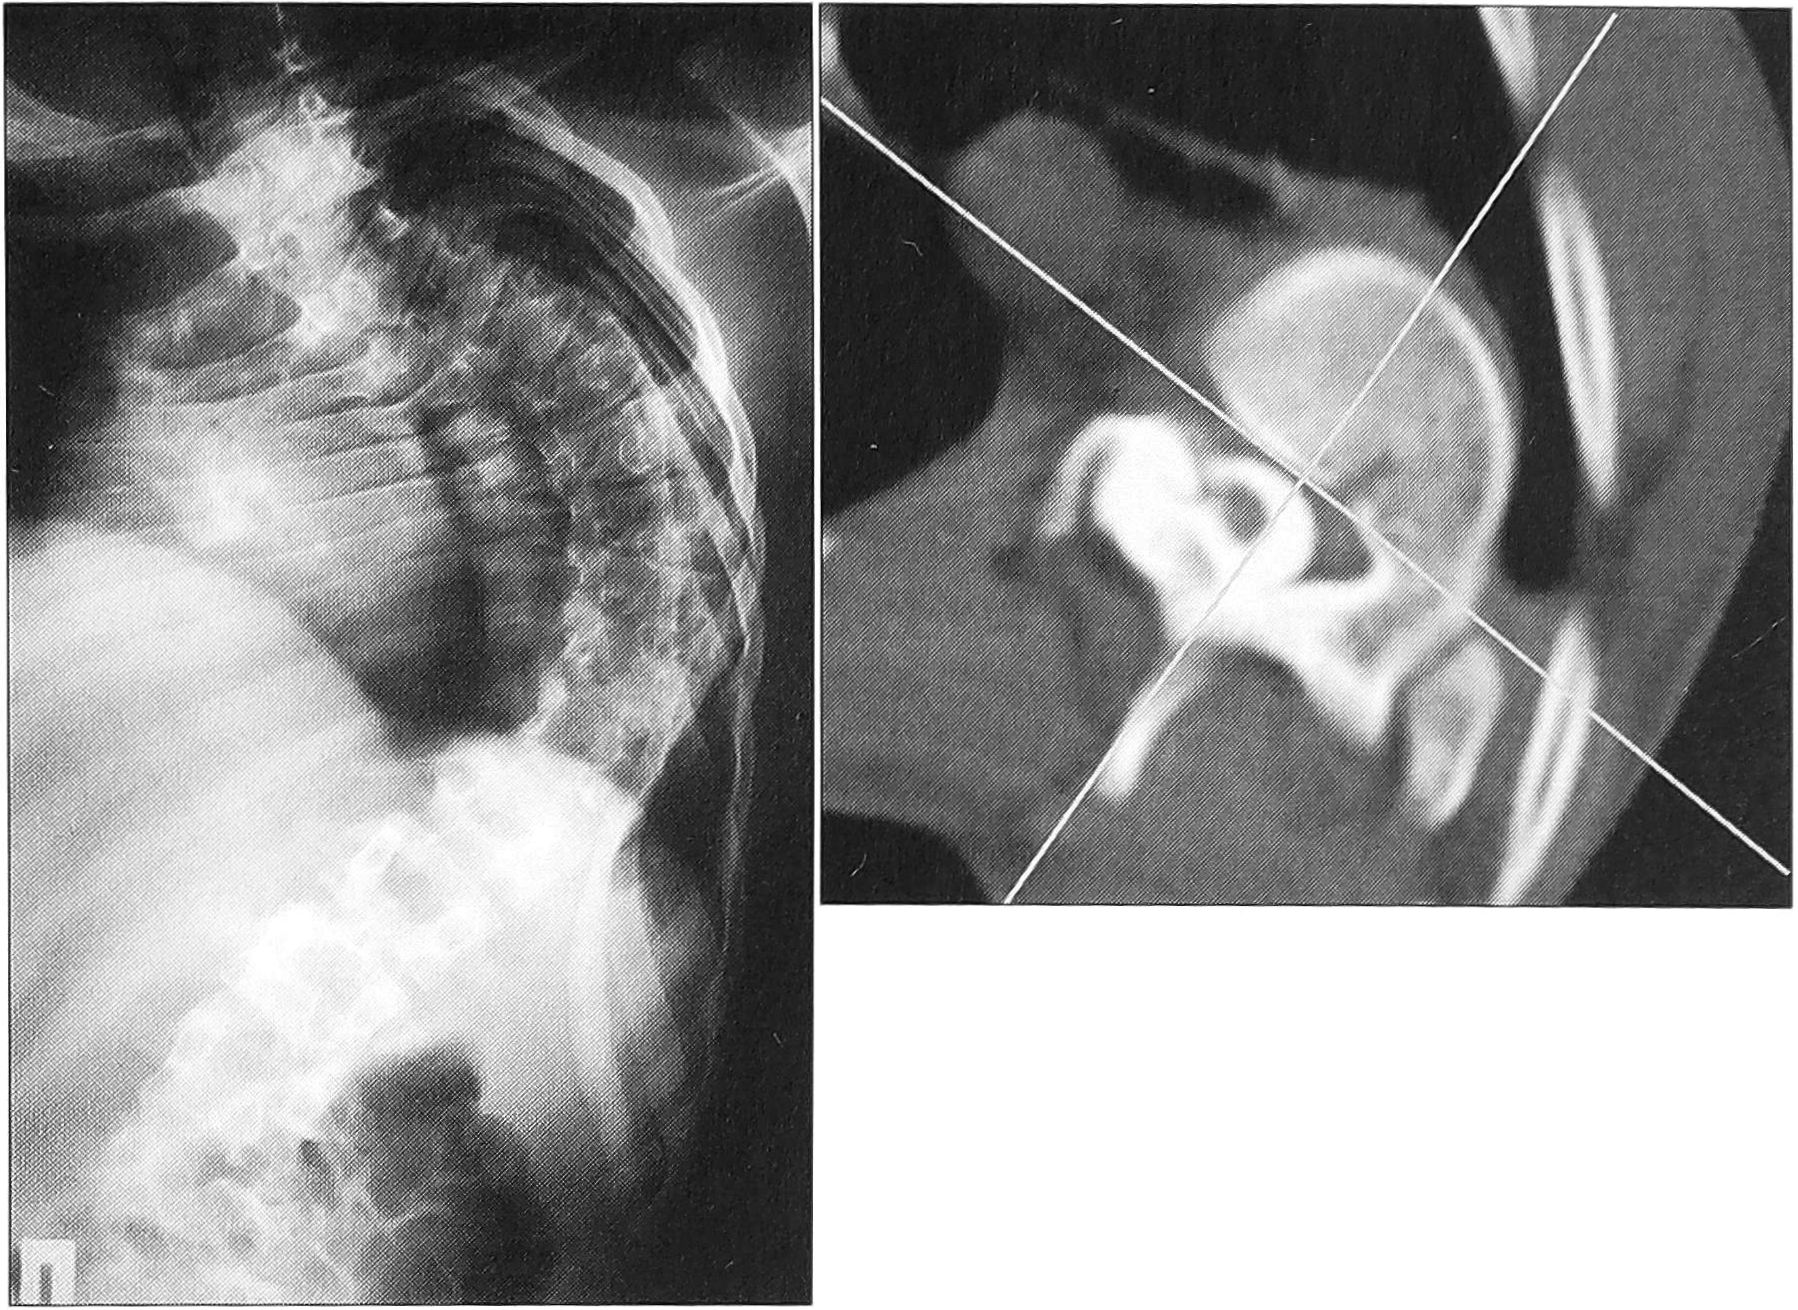

Рис. 3. Рентгенограмма позвоночника и КТ больного А. с левосторонним грудным сколиозом: величина общего угла основной дуги искривления 128°, ротация позвонка 45°.

Среднее абсолютное значение ротации, измеренной в горизонтальной плоскости, до оперативного лечения составило 24,5° (в группе больных с углом менее 80° оно равнялось 22,36°, с углом более 79° составляло 30,75°). Максимальное значение ротации, равное 45°, выявлено у больного А. с левосторонним грудным сколиозом с максимальной в исследуемой группе величиной общего угла основной дуги — 128° (рис. 3). После оперативного лечения среднее абсолютное значение ротации, измеренной в горизонтальной плоскости, составило 21,5° (19,5° у больных с углом деформации менее 80° и 30,0°— с углом более 79°), т.е. разница с предоперационным значением находится в пределах ошибки метода. Максимальная деротация, равная 17° (70,8%), получена у пациентки К. с диспластическим правосторонним грудным сколиозом. Существенная величина деротации позволяет считать ее истинной (рис. 4).

Рис. 4. КТ больной К. с правосторонним грудным сколиозом до (а) и после (б) оперативного лечения. Деротация вершинного позвонка 17° (70,8%).

Нотация вершинного позвонка, измеренная относительно верхнего нейтрального, до операции равнялась в среднем 24,85°, т.е. была сравнима с абсолютной. После оперативного лечения она составила 18° — разница 6,85° (27,56%), что несколько больше соответствующего абсолютного показателя. В целом полученная коррекция ротации у каждого пациента несколько больше, поскольку верхний нейтральный позвонок, относительно которого проводятся измерения, также меняет свое положение в пространстве. В одном случае абсолютная деротация вершинного позвонка составила 5° (19%), а относительная — 11° (48,8%), что было связано с увеличением ротации вершинного позвонка на 6° (рис. 5).